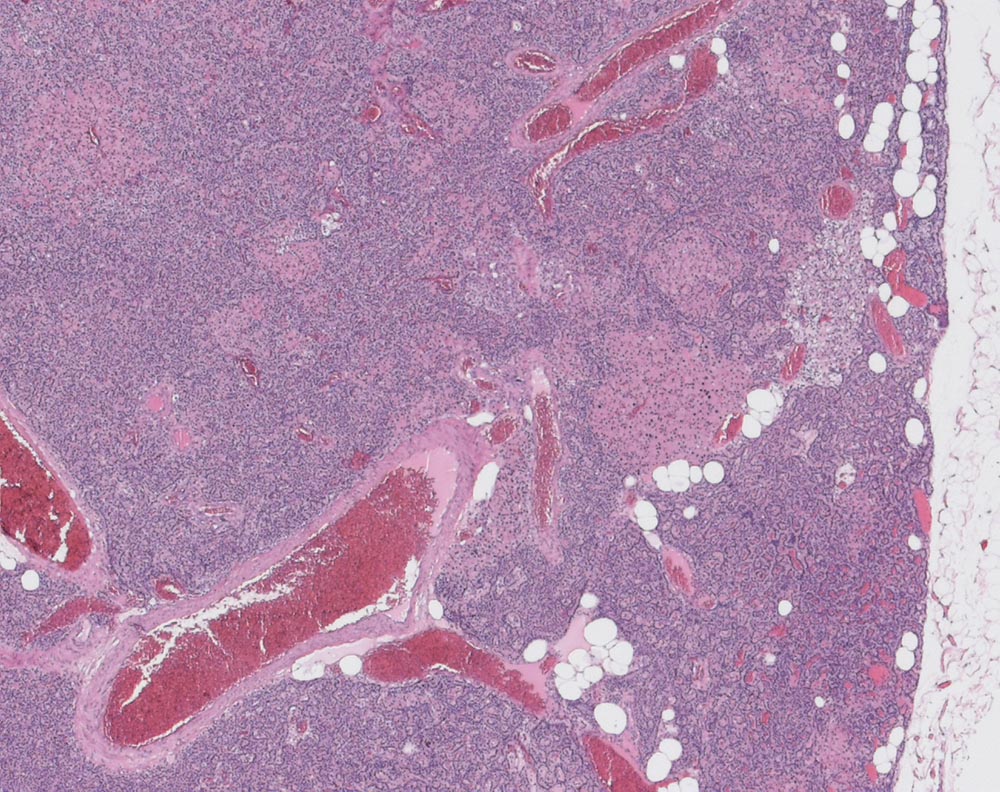

Das scharf begrenzte Adenom besteht überwiegend aus Hauptzellen und Nestern onkozytärer Zellen. Nur sehr wenig Fettzellen. Reste einer atrophen Nebenschilddrüse sind nicht erkennbar.

Primärer Hyperparathyreoidismus.

Rein histologisch ist der Befund nicht von einer Nebenschilddrüsenhyperplasie abgrenzbar. Nur zusammen mit der klinischen Angabe einer einzelnen vergrösserten Nebenschilddrüse und eines primären Hyperparathyreoidisimus lässt sich die Diagnose eines Nebenschilddrüsenadenoms stellen.